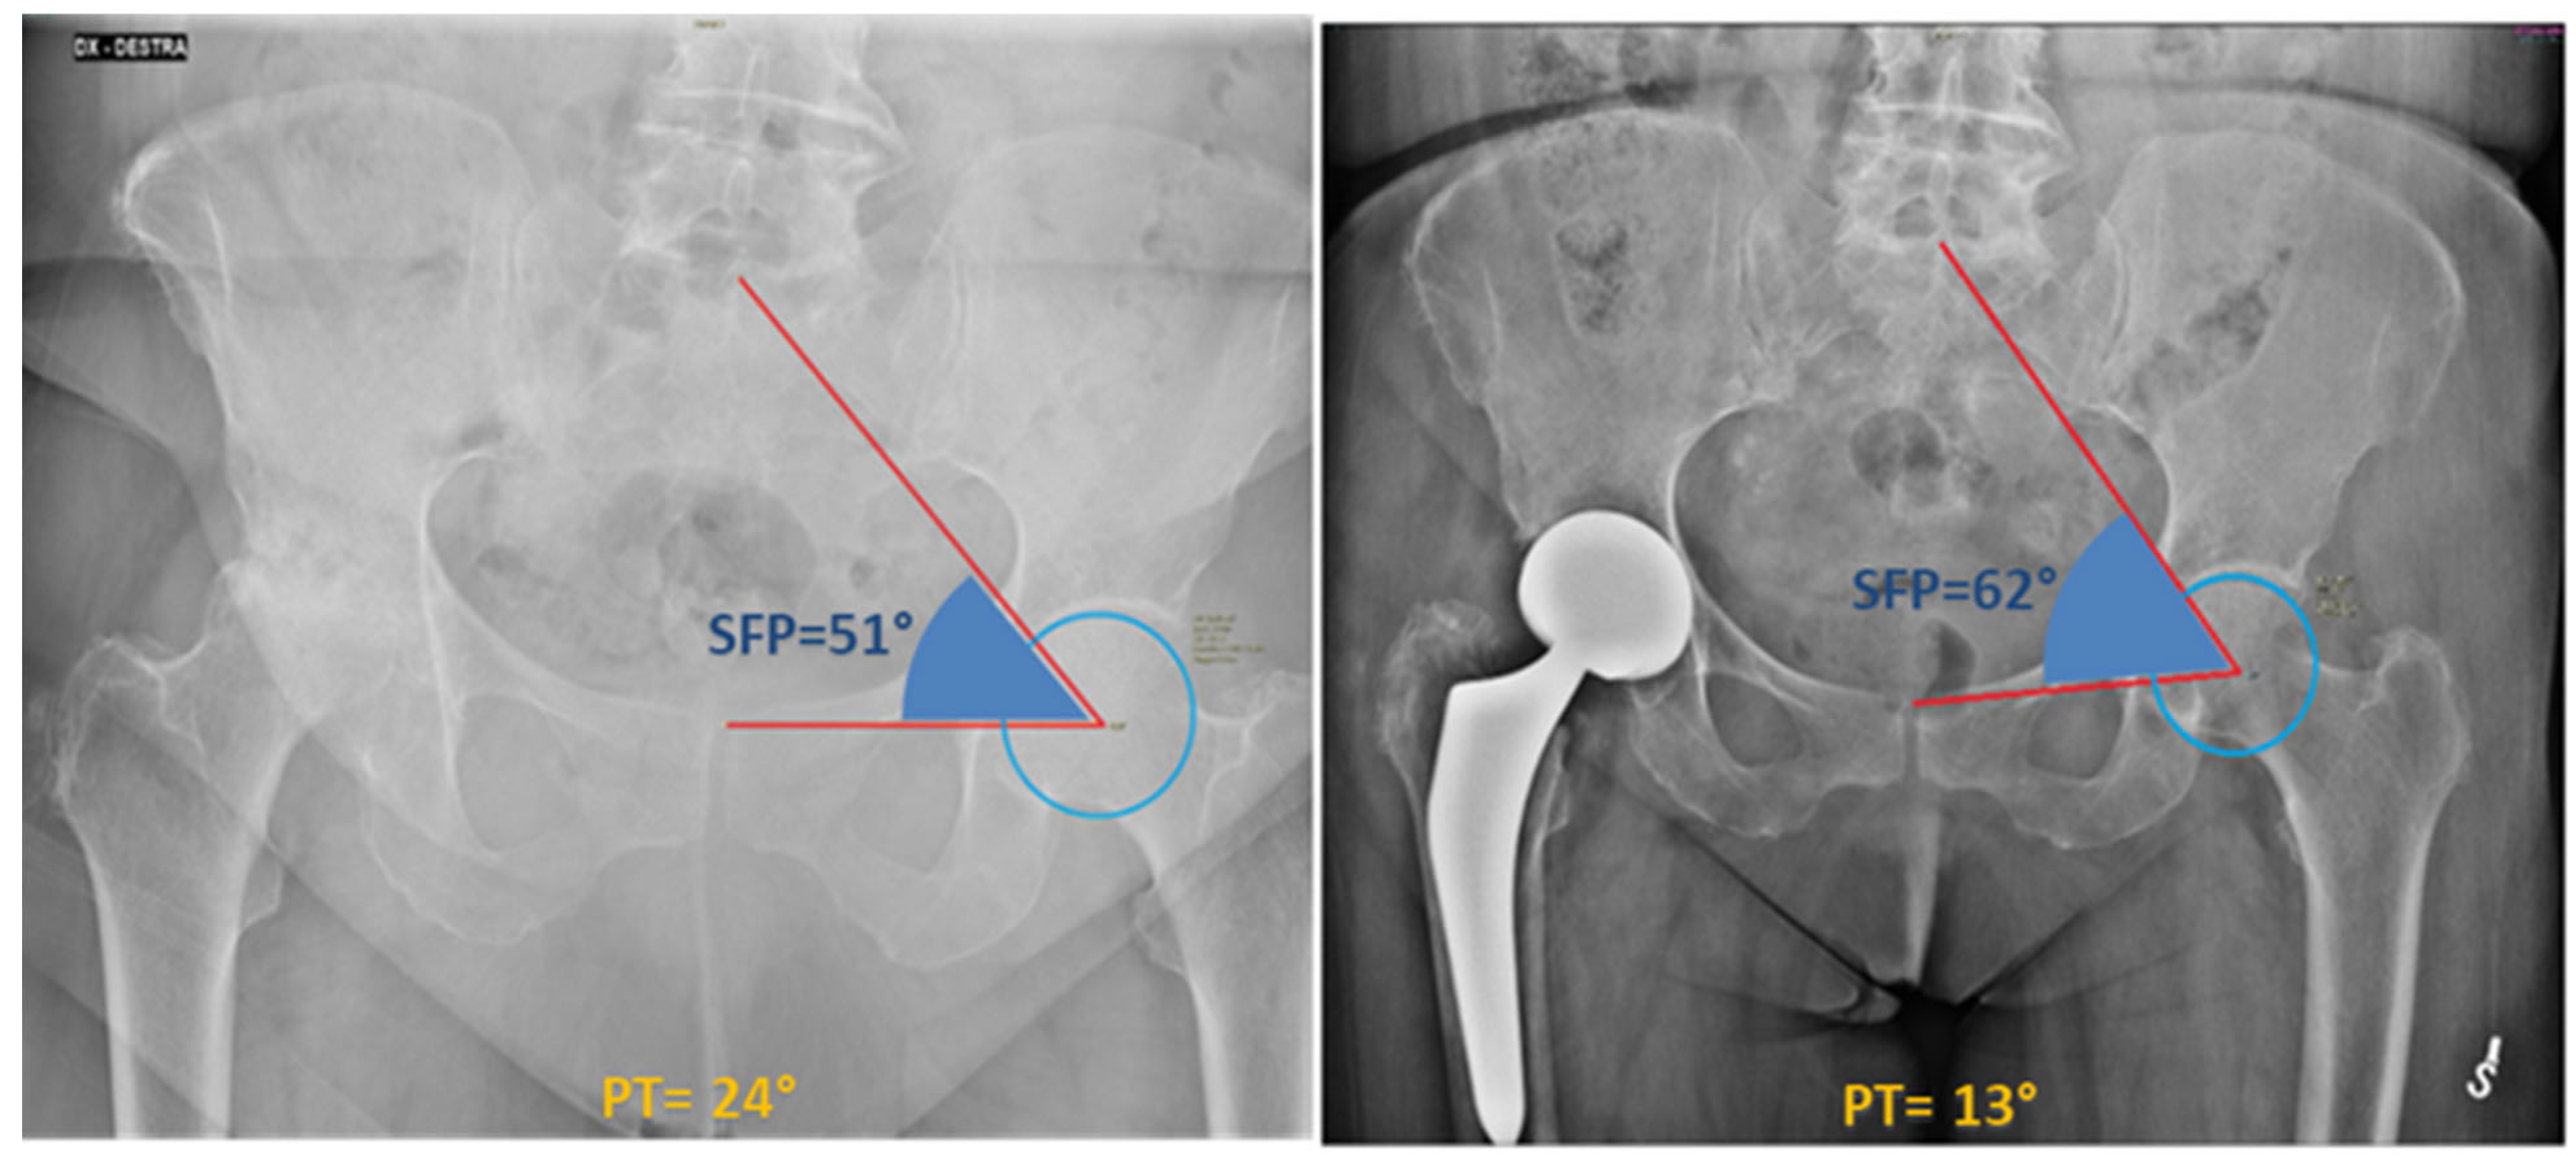

Sacro-femoro-pubic (SFP) angle was measured independently by two authors (G.G., E.M.) at the non-affected hip as shown in Figure 2 for each patient before surgery, immediately after surgery, and finally at the last available follow-up (FU) (average last follow-up time: 32.4 months). The angle was routinely measured on the non-prosthetic hip to assess any variations, as THA can shift the centre of rotation of the joint (often medially), thereby hindering the accurate measurement of the SFP angle: indeed, medializing the centre of rotation of the hip, as typically occurs in THA, would increase the SFP angle of the same hip, thereby simulating pelvic anteversion. Conversely, assessing the SFP angle on the contralateral hip inherently minimizes the risk of measurement bias. Excellent interobserver reliability was verified for the SFP angle (ICC superior to 0.9). Pelvic tilt (PT) was derived for each patient, according to the nearly-linear correlation with the SFP angle [5]: PT = 75 − SFP.

Figure 2. The SFP angle is measured on the coronal view of a standard anterior-posterior pelvic radiograph. The SFP angle, according to the description by Blondel et al. [5], is defined as the angle between the line passing through the midpoint of the upper sacral endplate, the centroid of one femoral head, and the upper midpoint of the pubic symphysis. This figure shows the different SFP angle between a preoperative (51°) and postoperative (62°) pelvis radiograph of a 77-year-old woman.